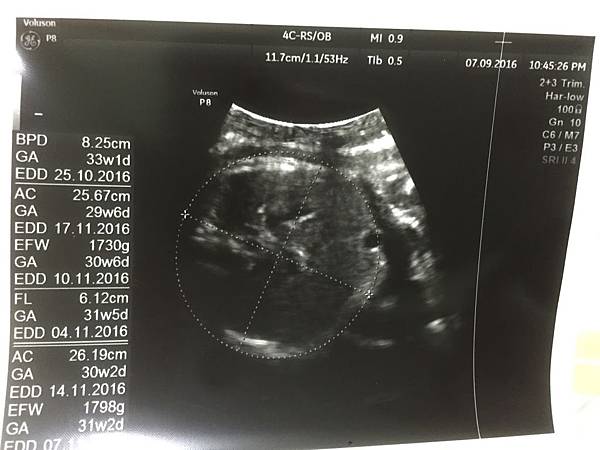

32週產檢,葉黃素體重來到1800公克~比上次足足多了500!

然後超音波照第一張我依然也是看不懂那到底是什麼

哈哈哈以後要是葉黃素問我我還真是回答不出來

這張很白癡想說記錄一下葉黃素的體重